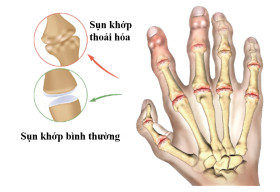

Chữa đau nhức xương khớp bàn tay, ngón tay thế nào